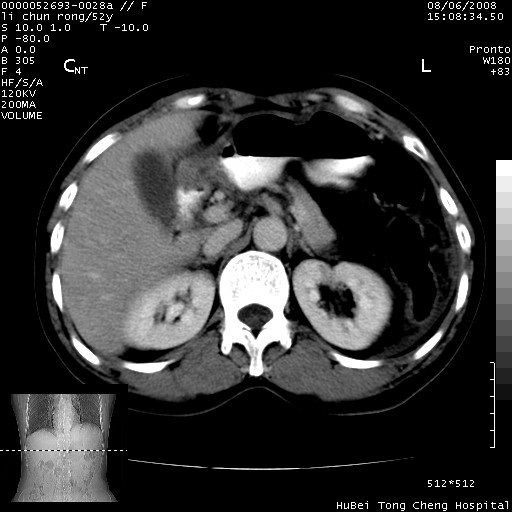

以下是引用云翔在2008-8-7 6:20:00的发言:[br]胰尾部囊性病变,考虑假囊肿,结合实验室检查疾病史

以下是引用zjzjr在2008-8-7 8:38:00的发言:[br]支持胰腺炎伴假囊肿形成,左肾小囊肿.少量腹水.

以下是引用随光逐影在2008-8-7 9:12:00的发言:[br]1)考虑胰腺炎伴假性囊肿形成可能性大;胰腺囊腺瘤待排。2)左肾小囊肿。3)少量腹水。